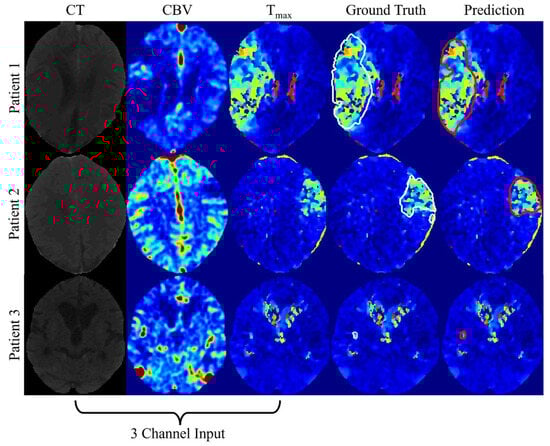

| CT, CBV, Tmax | 0.53 ± 0.22 | 0.56 ± 0.19 |